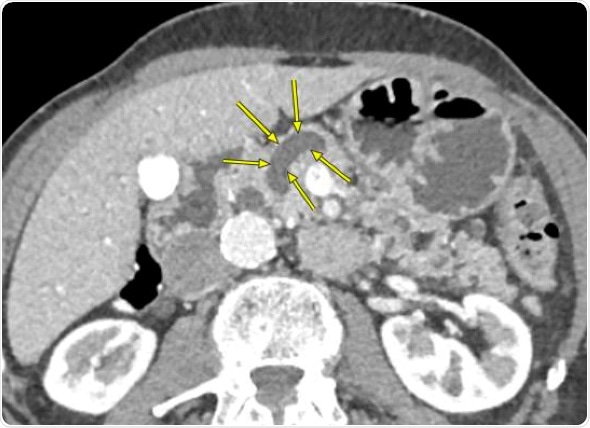

CT scan of a pancreas that shows enlarged pancreatic duct. Credit: Johns Hopkins Medicine

The pancreas is shaped vaguely like a revolver, with a duct --normally about 3 millimeters in diameter -- that runs all the way down the barrel of the gun and carries digestive enzymes. When inflamed or populated by cysts or other growths, the duct enlarges.

Then, the researchers gathered information on the widths of each pancreatic duct in the 901 patients using CT scans and MRIs taken for any reason within 30 days prior to the patients’ surgeries.